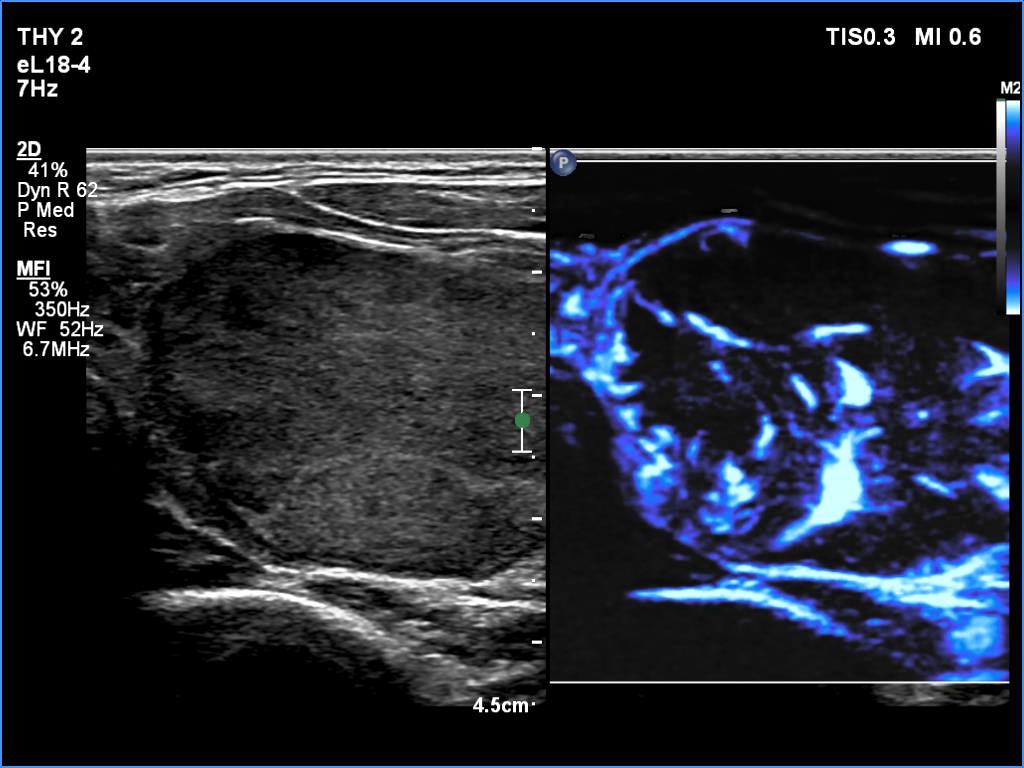

The echogenicity of the nodule - case 365 (ultrasonographic picture 9)

Five years after the first examination

Left lobe, transverse scan, microflow imaging. The nodule has both perinodular and intranodular vessels.